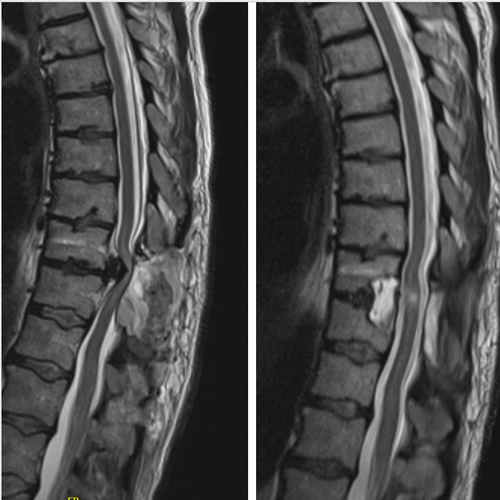

Spinal stenosis (Lumbar) Spinal stenosis (Cervical) Spinal stenosis (Thoracic) Lumbar Disc Herniation Spondylolisthesis Cervical Foraminal Stenosis Vertebroplasty Lumbar Fusion Anterior Cervical Fusion (ACDF) Posterior Cervical Fusion Thoracic Fusion Revision Lumbar Fusion Surgery Facet Joint Cyst Spinal Tumour Minimally Invasive Lumbar Fusion (XLIF) Minimally Invasive Lumbar Fusion (ALIF) Lumbar Fusion (TLIF) Thoraco-lumbar Fusion Lumbar Corpectomy Complex Lumbar Spine Surgery (Spino-pelvic fixation) Complex Cervical Spine Surgery Complex Thoracic Spine Surgery Occipito-cervical Fusion Minimally invasive surgery for thoracic disc herniation Other Related Topics